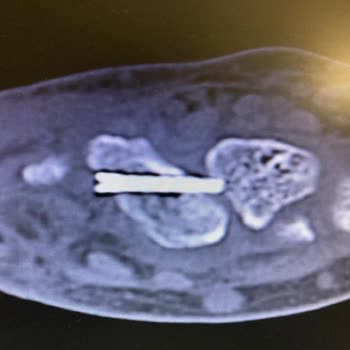

Büyükçekmece Kolan Hastanesi ve baş hekim yardımcısı op. Dr. F*** M*** Ü*** sizinle mahkemede görüşeceğiz. Kırık ayağın iyileşti diyerek çalışabilir raporu verdin! 1. Platin yanlış takılmış ayağım 8 cm önde 2. Platinin vidalarından biri eklemime saplanmış. 3. Yaran kapanıyor dediğin yer et parçası değil enfeksiyon bunu bilmemiş olman ne garip? 4. Sizin aylarca benden almadığınız kanımda enfeksiyon çıktı. 5. Enfeksiyon kırık kemiğime bulaştığı söyleniyor ve kaynadı dediğin kırık kaynamamış bana açık yaranı sarıp işe göndereceğiz demiştin oysa ayağımı tutan kaynayan kemik değil platinin kendisi. Ayağını bas korkma diyordun ya iyi ki ayağıma çok yüklenmedim. Çünkü platinin kırılma ihtimali var. Yani kırılsaydı belkide ömür boyu sakat kalacaktım ya da merdivenlerden yuvarlanacaktım ya da yolda yürürken arabanın altında kalacaktım. 6. Benim röntgenimi çekmeden çalışır raporu vermen yürümeye korkuyorsun demenden atarlı giderli konuşmadan belliydi.  enfeksiyon olduğunu çok iyi biliyordun bu ayağı düzeltemeyeceğinide biliyordun. 7. Benim ayağımın sakat kalma ihtimali varmış. Ameliyat olacağım niye biliyor musun prof Dr. Taktığın daha doğrusu takmayı bile beceremediğin platinler çıkarılacak. Kemiğime enfeksiyon bulaşmış senin sözde aylarca muayene edipte göremediğin enfeksiyon için mücadele verilecek. Enjeksiyon yenilirse ikinci ameliyat olacağım kemik nakli kas nakli bunların 1 yılı bulacağı söyleniyor ve bir garantisi yok prof Dr. Hani diyorum ya fizik tedaviye ihtiyaç yok ayağın iyi şimdi çok iyi anlıyorum niye fizik tedaviye göndermediğini sen gerçekten efsanesin. Yaraya su dökebilirsin demenden belliydi en başından anlamalıydık. Gerçi neyi anlayacaksın telefondan asistanın bana çalışır raporu vereceğiz dediğinde bu işin buraya geleceği belliydi. Sizin hiçbir zaman göndermediğiniz temografide çıktı bunlar. Senin çektiğin normal röntgen de bunlar çıkmıyor yeni Dr. Bu röntgenle bir şey belli olmaz birçok cihaza gönderildim. Baltalimanı op. Doktoru Yani kısaca bu işin uzmanı. Biz sana demiştik ameliyattan sonra bizim yerimiz uzak başka hastanede ilk ameliyattan sonra tedavi olalım. Sen ne dedin Ahmet'in ölüsü de dirisi de benim, ölüyü de diriye de gördük sayende. Kibrin hasmı Allah'tır. İlk ameliyattan sonra benim işim buraya kadar bu kırık beni aşar daha iyi hastaneye ve Dr. Gösterin deseydim bunlar başıma gelmeyecekti.

19.06.2023 tarihinde iş kazası geçirdim, ayağım kırıldı. Büyükçekmece Kolan hastanesinde İlk ameliyatım yapıldı. İlk ameliyattan sonra dikişler alındı. Daha sonra Dr. Bana duş alırken ayağına su dökebilirsin dedi. Bu olay yaramın intihaplanmasına sebep oldu. İkinci ameliyat yapılmasına karar verildi. Ancak doku nakli ameliyat hüsranla bitti. Ameliyatın başarısız olma sebebi platindeki vidanın olmasıydı. Sonra vidayı aldılar. Madem vidayı alacaktınız niye ameliyat yaptınız? Bu ameliyattan sonra ki dönemde verilen raporum hastane tarafından onaylanmadığını SSK tarafından öğrendim. Hastaneyi aradım Dr. Asistanına durumu anlattım. Kendisi bana 27.11.2023 tarihinde geleceksin biz sana çalışır raporu vereceğiz dedi. Şimdi soruyorum hastaneye girmeden röntgen çekilmeden telefondan çalışır raporu vereceğiz denilebilir mi? İlk ameliyat olduğumda hastane uzak olduğu için biz evimize yakın hastane istiyoruz dediğimizde Dr. Bize senin ölünde dirinde benim demişti. Son röntgende vidalar dolmadığını kırık yerlerin tam dolması için zamanın olduğunu yavaş yavaş yürümemi ancak ramboluk yapmamı söyleyen Dr. Ne olduysa bu asistan ile paramı alamıyorum onay niye verilmiyor dedikten sonra hastaneye gittiğimde bana yara açık ayak şiş fizik tedavi olunmamış ayağa çalışır verdi. Üslubu davranış biçimi bir ay önce ki Dr. İle yakından uzaktan olmadı beni hastaneye götüren şirketin sağlık görevlisi tarafından bizzat görüldüğü kendisinin de buna bir anlam veremediğini bilmemizi istiyorum. Bu olaydan sonra şirketin sağlık görevlileri bana bu ayakla iş başı yapmamın mümkün olmadığını ayağımda ödem olduğu yaranın açık olduğunu fizik tedavi olunması gerektiğini belirtildi. Ben bu Dr. Dan şikayetçiyim. Büyükçekmece Kolan hastanesinde ki, Op. Dr. F*** M*** Ü*** hakkında soruşturma açılmasını arz ederim. Saygılarımla. Dip not. Sağlık Bakanlığı da dahil olmak üzere şikayet etmemiz gereken ne kadar yer varsa şikayet yapılacaktır.